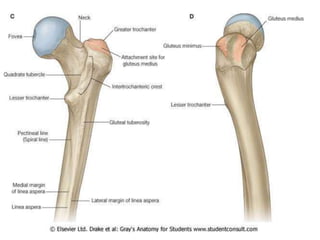

GREATER TROCHANTER

• It’s a quadrilateral elevation, projecting

upward from the lateral aspect of the

junction of neck and shaft.

• Its upper & posterior part is bent

backwards & medially and overhangs the

neck.

• Its lateral surface has an oblique rough

ridge which separates 2 smooth areas.

• It has the following features:

–Its lateral surface is convex.

–Its upper & posterior borders are free.

–Its highest point is in its posterosuperior angle.

–Its medial surface has a deep depression called

the trochanteric fossa for insertion of obturator

externus..

–Its posterior part presents the apex or tip of

greater trochanter, which gives connection to

the piriformis.

– A shallow depression above and in front of

trochanteric fossa for insertion of obturator internus

together with the gemellus superior and gemellus

inferior.

– It is quadrilateral and split diagonally by an oblique

ridge into the upper and lower triangular regions.

• The ridge gives connection to the gluteus medius

muscle.

– The triangular regions- anterior and posterior to the

ridge are associated with the trochanteric bursae of

the gluteus medius and gluteus maximus,

respectively.

LESSER TROCHANTER

• It is a conical projection rising from the

posteromedial surface of the neck-shaft angle. It is

directed medially.

– Its apex gives connection to the psoas major.

– Iliacus is connected to its base on the front.

• Three lines radiate from the lesser trochanter

– One runs upwards & medially below the neck.

– 2nd is pectineal line; it runs downwards & gives

attachment to the aponeurosis of the pectineal muscle.

– 3rd line runs upwards & laterally and forms the lower half

of the “Intertrochanteric crest”